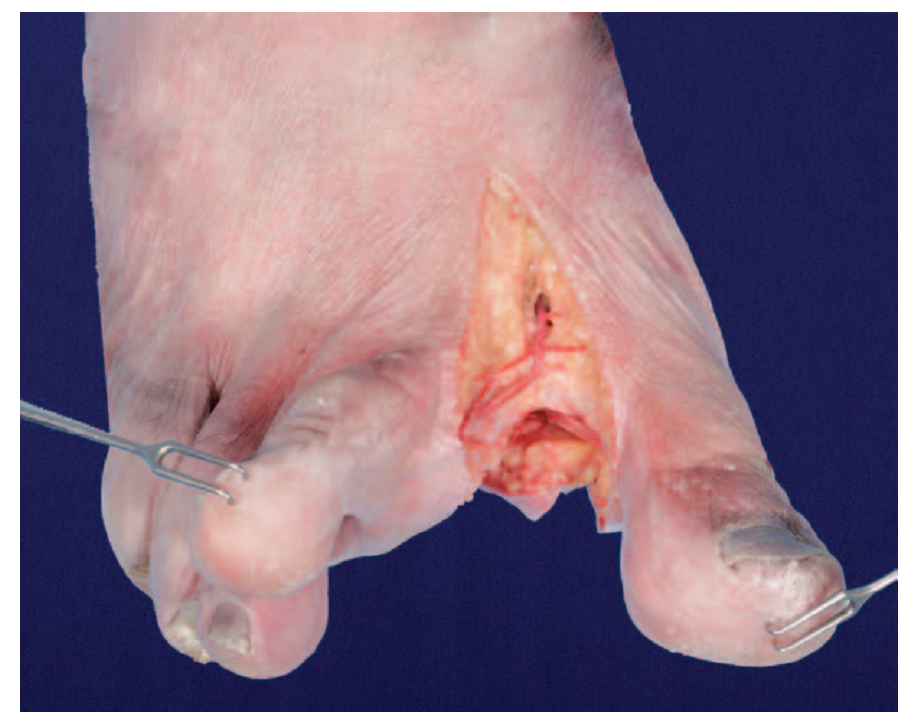

在切取血管蒂时,术者常采用顺逆结合的分离方式。如果第1跖背动脉是A1型,血管由足背动脉分离出的位置常常比较表浅,切断血管比较容易。当血管来自足底动脉时,需要将第1骨间背侧肌的胫侧头切开,牵拉向腓侧,从第1跖骨间隙内结扎切取,不可以携带足背动脉为蒂进行组织移植或移位。

对于B1型第1跖背动脉,可以第1跖背动脉为蒂分别切取拇甲瓣或第2足趾。对于B2a型,临床上以第1跖背动脉为蒂只能切取拇甲瓣、拇指腓侧皮瓣等第1跖背动脉血供分布范围的组织瓣。B2b型则只能以第1跖背动脉切取第2趾胫侧皮瓣或者第2足趾,对于此型患者要切取拇甲瓣时则需要向深处解剖第1跖底动脉,以其为蒂取拇甲瓣。B2型第1跖背动脉虽然解剖比例不高,但是如果对其没有足够的认识而选择不当,将会导致严重后果。B3型不能以第1跖背动脉为蒂切取拇甲瓣或者第2足趾移植。

此外,本研究发现第1跖背动脉并不穿过第1骨间背侧肌肌肉内部,而是在第1骨间背侧肌胫腓两头之间,在两头的交汇处绕过第1骨间背侧肌的胫侧头穿入至其跖侧,位于第1骨间背侧肌和第1跖骨体之间的间隙内紧贴第1跖骨体走行。手术中解剖游离第1跖背动脉时,仅需切断第1骨间背侧肌胫侧头,将其向腓侧牵拉翻起,即可清晰显露肌肉与跖骨体之间的第1跖背动脉。